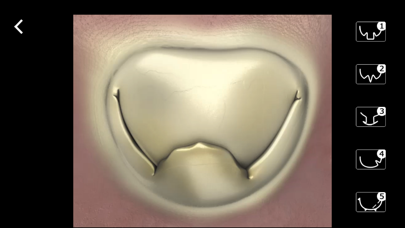

Mitral & Tricuspid Valves

от Edwards Lifesciences

TEE Evaluation of the Mitral and Tricuspid Valves